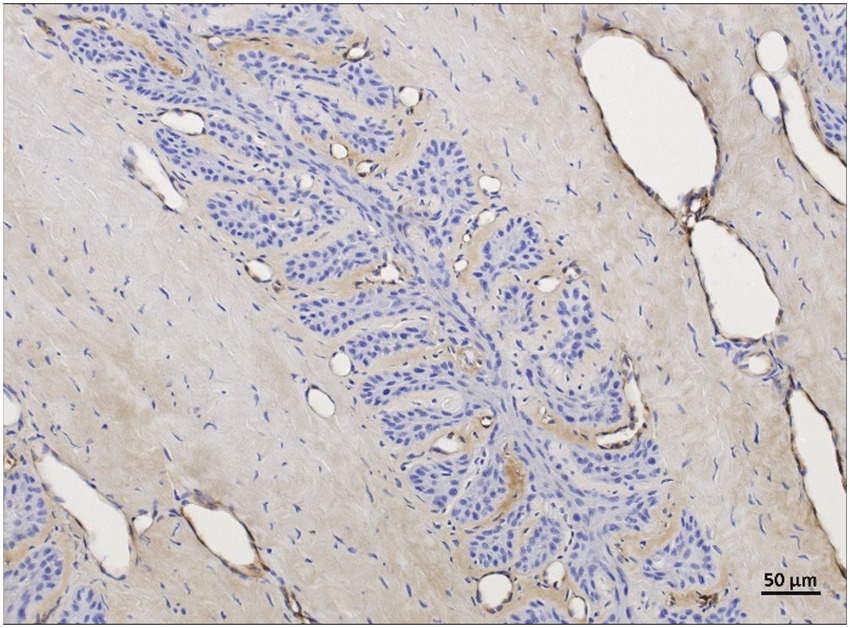

Figure 9

Histological image split into two panels, labeled A and B, showing tissue sections with labeled structures: PDL, SDL, and SEL. Arrows and arrowheads indicate specific points of interest. The image has light brown and blue staining, with magnification indicated by a 20-micrometer scale bar.

Figure 9. vWF-IHC (DAB counterstaining) in lamellar hoof tissue from fresh (A) and frozen-thawed-perfused (B) samples. Labeled vascular endothelial cells in regions 2 and 5 (assignment to regions see Section 3.7) in the non-laminitis control cohort. PEL, primary epithelial lamella; PDL, primary dermal lamella; SEL, secondary epithelial lamella; SDL, secondary dermal lamella; open arrow: vWF-positive axial blood vessels within the PDL, black arrowheads: vWF-positive capillaries in the SDL, open arrowheads: vWF-positive lamellar arterioles/ venules, A four-pointed star shape with elongated, narrow arms extending outward from the center. The star is solid black with a subtle blur effect, giving it a soft appearance. black stars: vWF-positive dilated blood vessels in the PDL. Light microscopy, (A,B) scale bar = 20 μm.

The mean score for immunostaining specificity of anti-vWF antibody in the non-laminitis control cohort was 3 in the fresh group, 3 in the frozen-thawed group, and 2.7 (Range: 2.3–3) in the frozen-thawed-perfused group. The mean score for immunostaining specificity of anti-vWF antibody in the laminitis cohort was 2.7 (Range: 2.3–3) in the fresh group, 3 in the frozen-thawed group, and 2.8 (Range: 2.6–3) in the frozen-thawed-perfused group (Figures 9A,B).